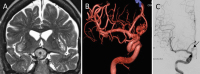

Neurovaskuläre Therapieoptionen bei komplexen Aneurysmen der Arteria carotis interna // Neurovascular therapeutic options in complex intracranial aneurysms

Journal für Neurologie, Neurochirurgie und Psychiatrie 2021; 22 (3): 128-134 Volltext (PDF) Summary Praxisrelevanz Abbildungen